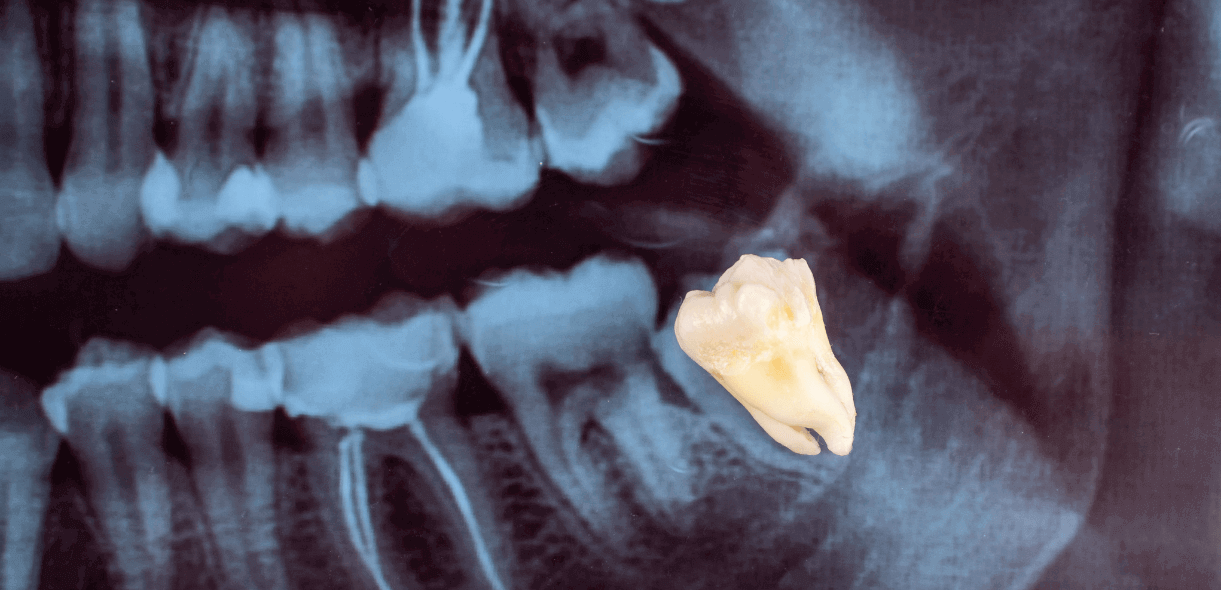

Wisdom teeth, also known as third molars, typically emerge in late adolescence or early adulthood. While some individuals experience no issues with their wisdom teeth, others may encounter problems such as impaction, overcrowding, or improper alignment. In such cases, a dentist may recommend wisdom tooth extraction to prevent potential complications and maintain oral health.

Before undergoing wisdom tooth extraction, patients often consult with their dentist or oral surgeon for a thorough examination. X-rays may be taken to assess the positioning of the wisdom teeth and determine the best course of action. The dentist will discuss the extraction process and anesthesia options and address any concerns the patient may have.